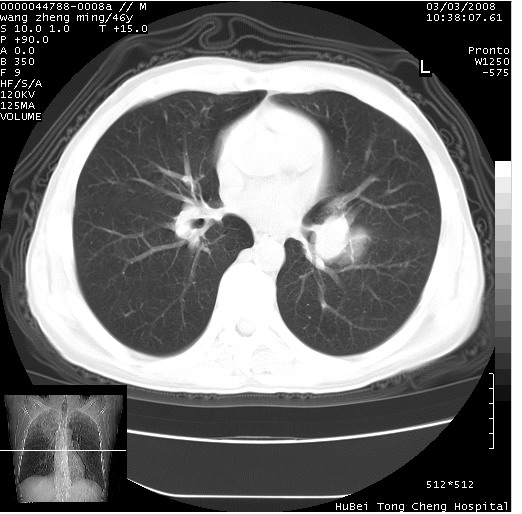

以下是引用卜一在2008-3-22 1:37:00的发言:[br]右肺实质性肿块,边缘不整,明显见毛刺征 分叶征及胸膜凹陷征,右上叶支气管明显变窄,远端散在的片状 斑片状实变影。另:左肺门较大肿块,支气管受累 变窄,远侧见阻塞性肺炎。纵隔内见肿大淋巴结。多考虑:右肺周围性肺癌伴左肺门 纵隔淋巴结转移!